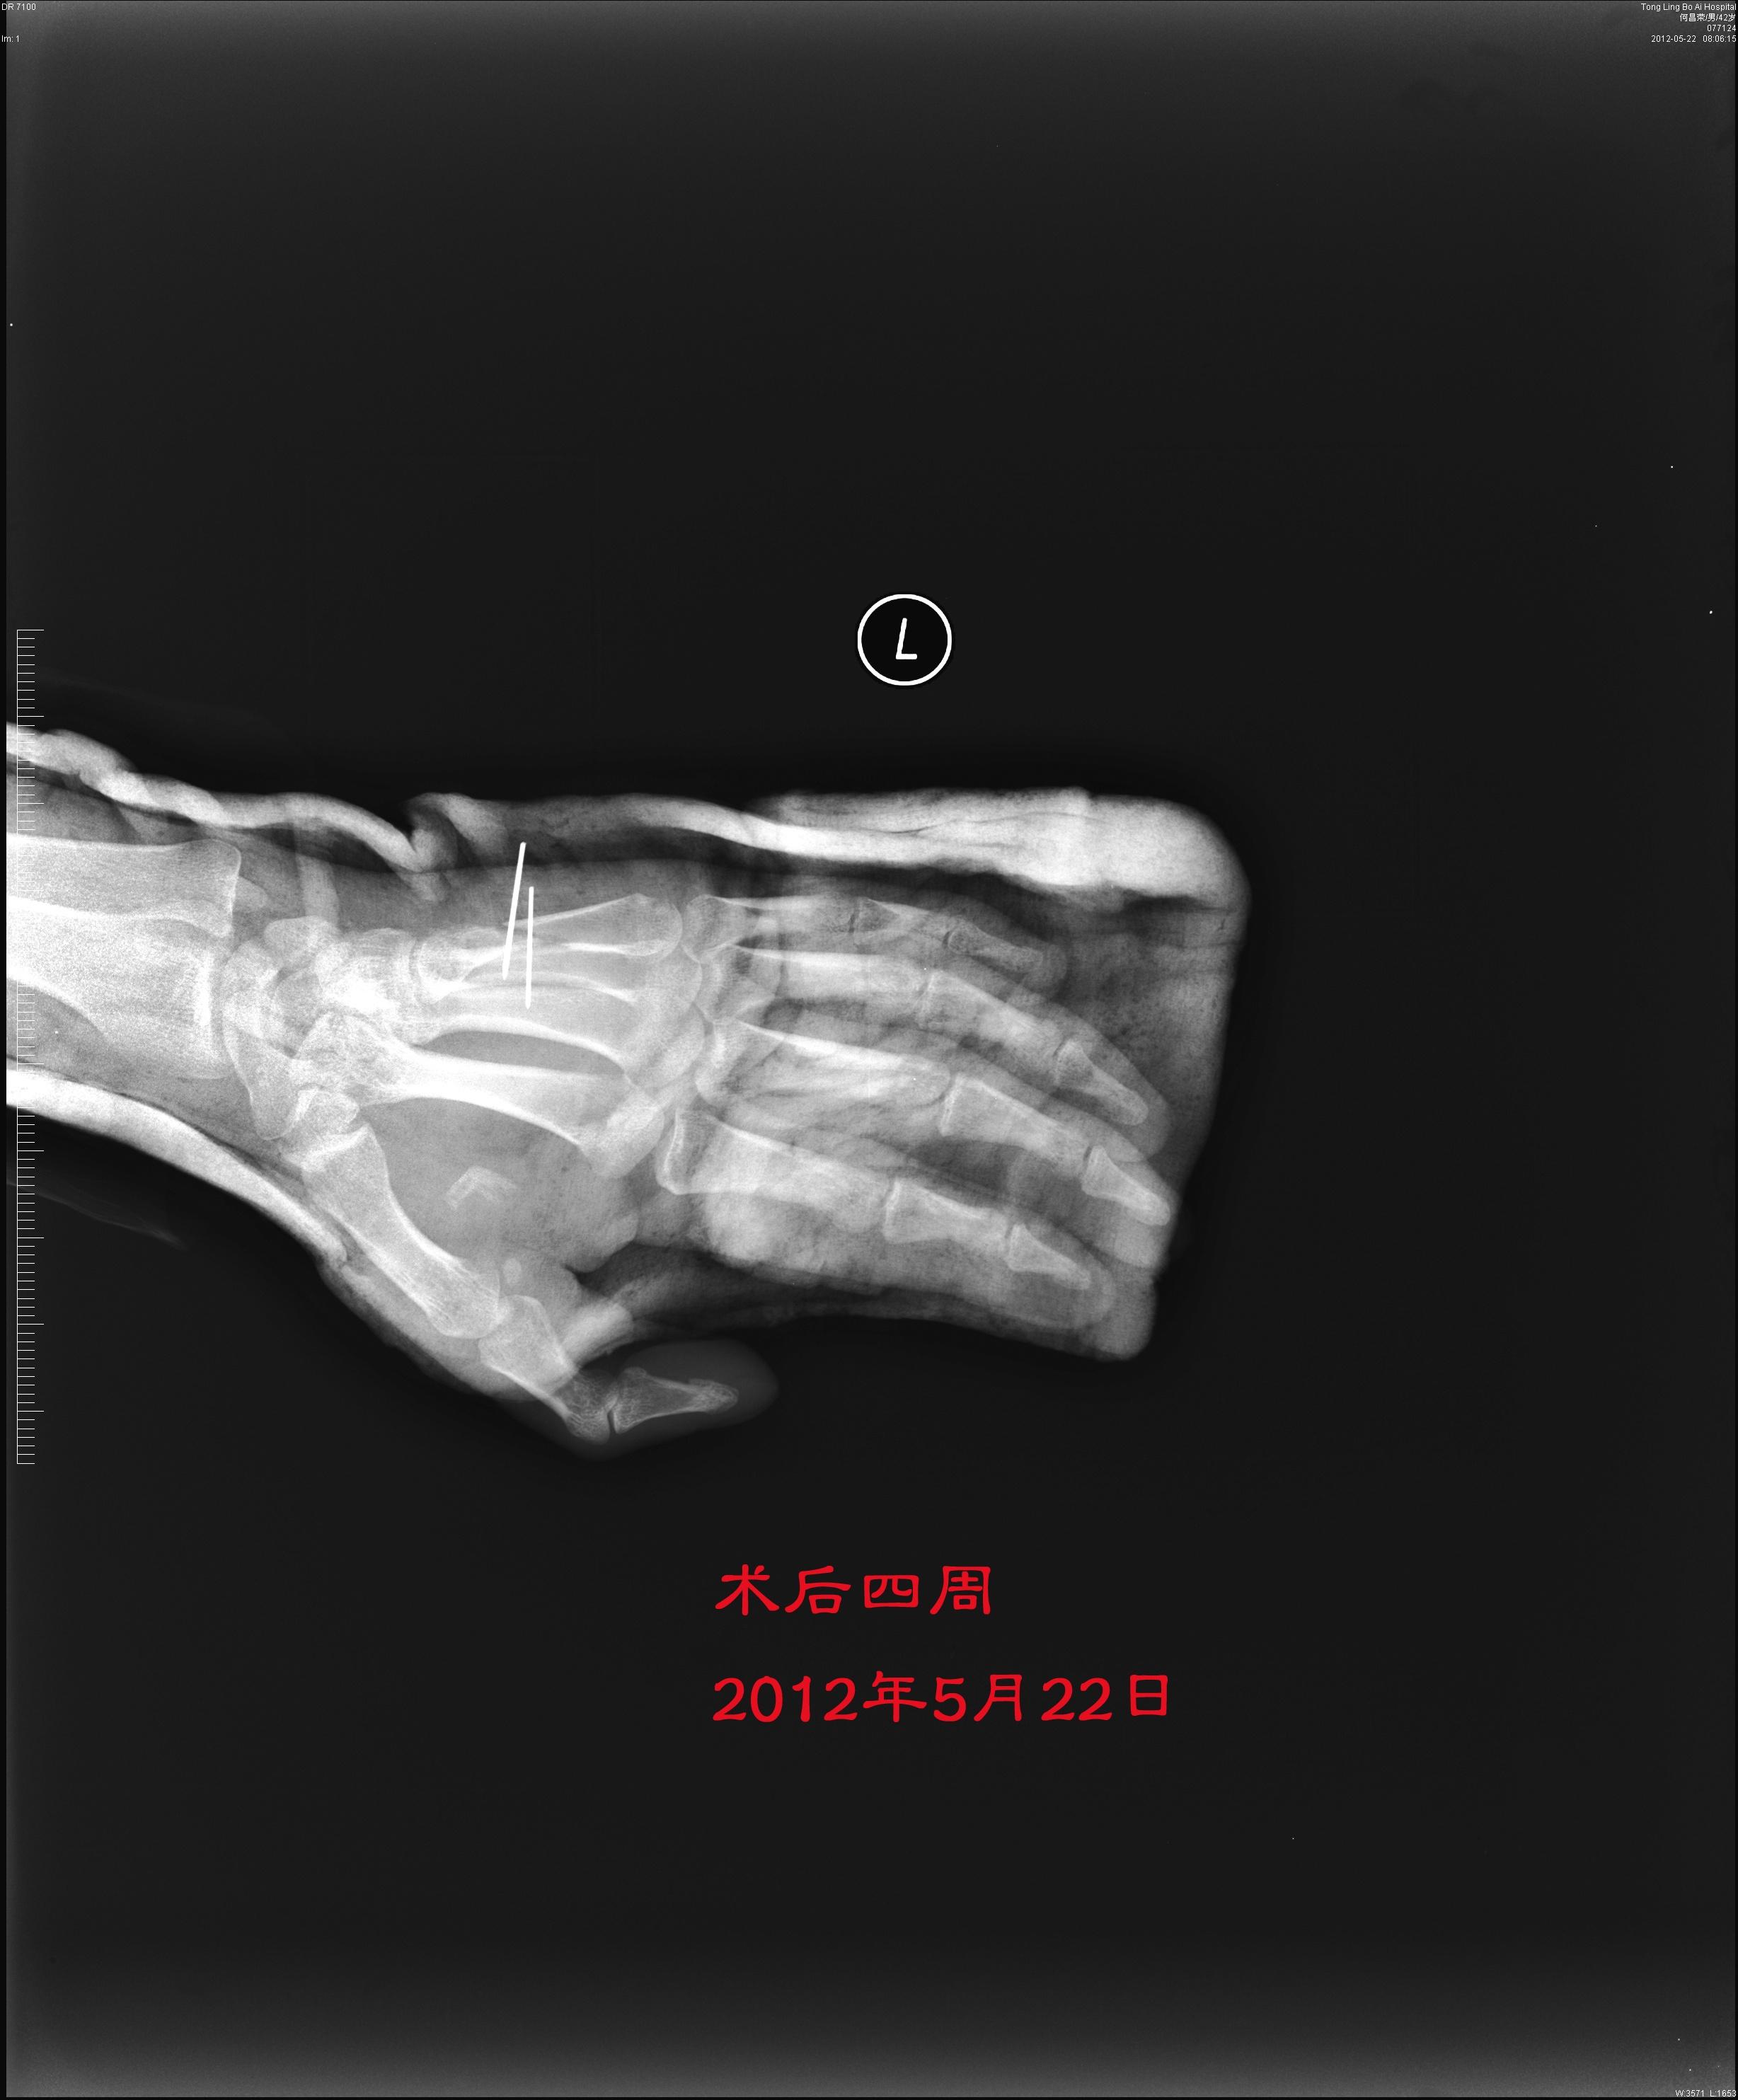

开放性第五掌骨长斜型骨折克氏针固定是否需要重新固定

图片尺寸2456x2968